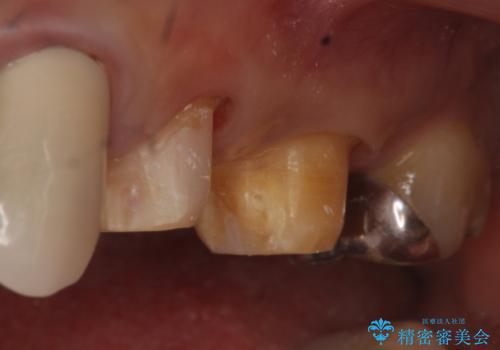

- 昔治療した左上56の延長ブリッジをきちんと治療しなおしたいといらっしゃった方の症例です。

古いブリッジを除去後、オールセラミッククラウンによる補綴を行いました。